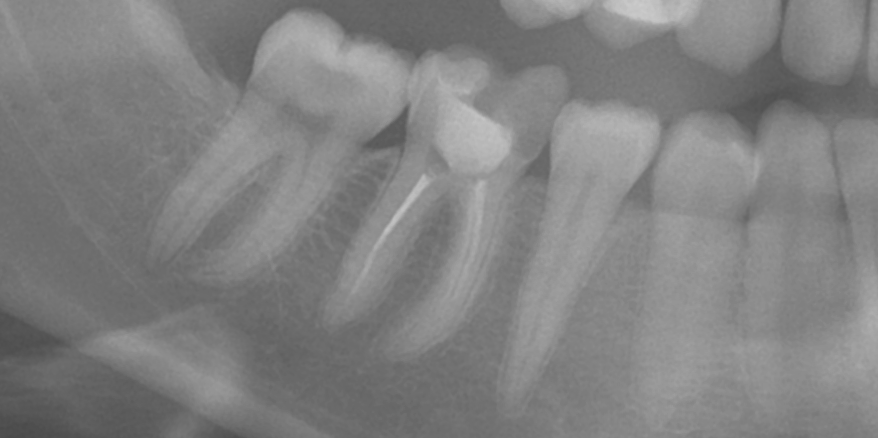

Dantų kanalų gydymas